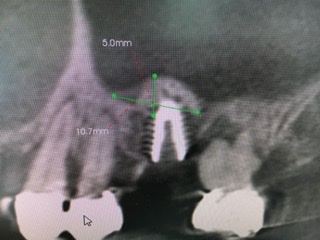

今回のケースは残存骨の高さは6ミリ

インプラント体は径5.5ミリ、長さ8.5ミリ

結果は画像にあるように皮質骨2箇所に固定が取れ正しくバイコーチカルが得られ値も79出て良かったです。充分なドーム状の挙上、更に裾野の広い形態、また詰め過ぎず、余裕持たせるが、成功の秘訣だと執刀医の須田医師は言います。